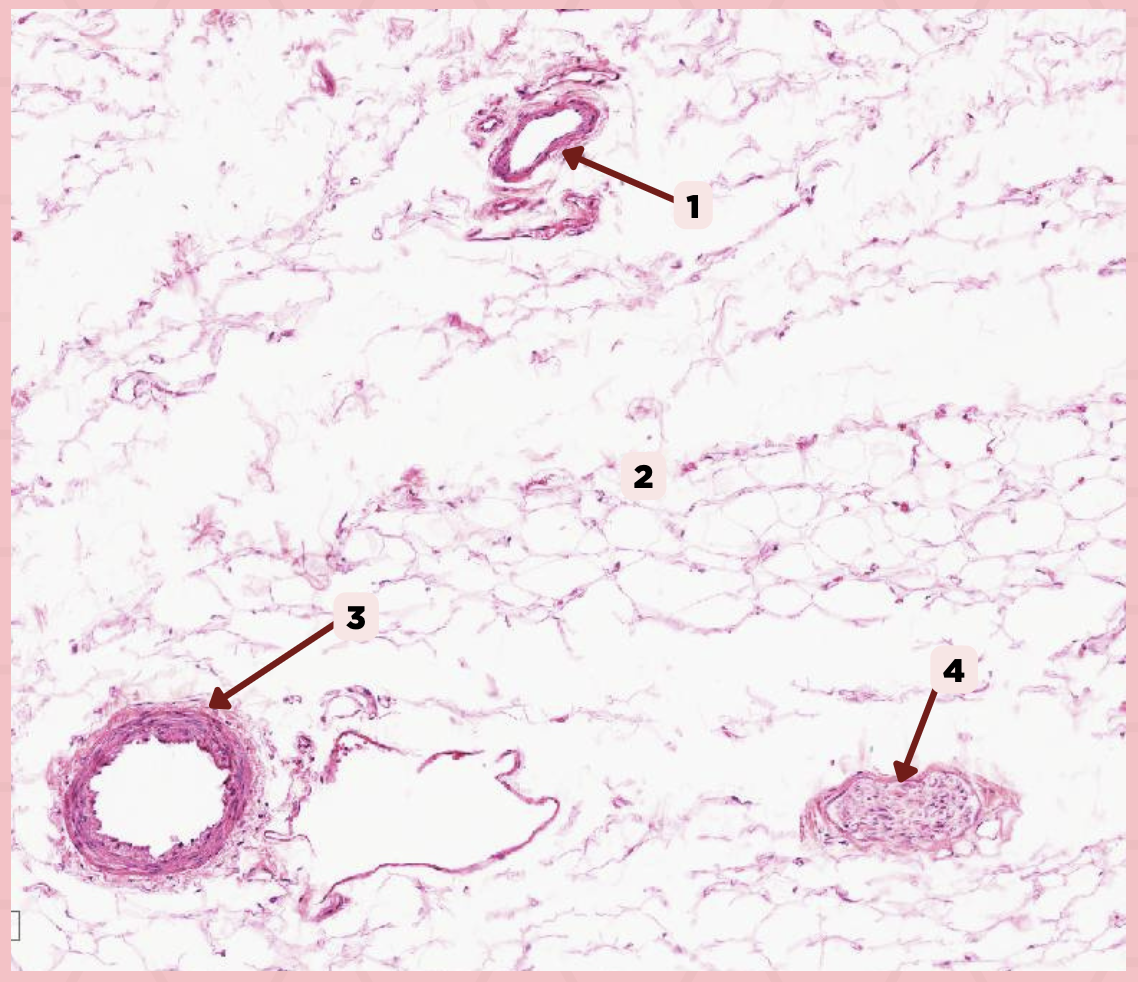

Cheek

Identify the specimen.

Vein

Identify the structure labeled as 1.

Hypodermis

Identify the structure labeled as 2.

Artery

Identify the structure labeled as 3.

Nerve

Identify the structure labeled as 4.